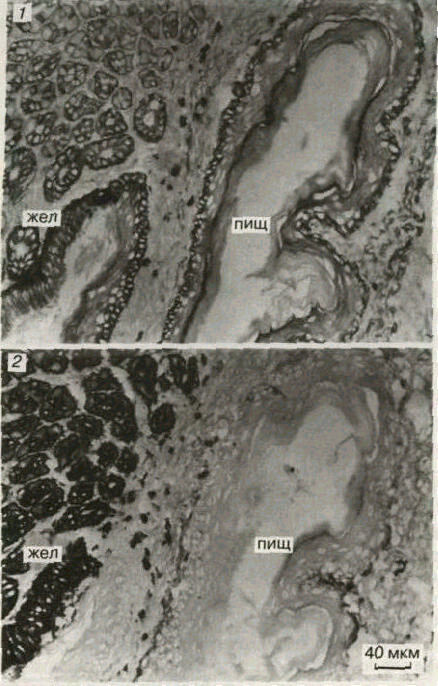

Рис. 3. Последовательные срезы через желудок (жел) и пищевод (пищ) мыши, окрашенные двумя моноклональными антителами: 1 - первое моноклональное антитело реагирует с эпителием пищевода и слабее с эпителием желудка; 2 - второе моноклональное антитело реагирует только с эпителием желудка.